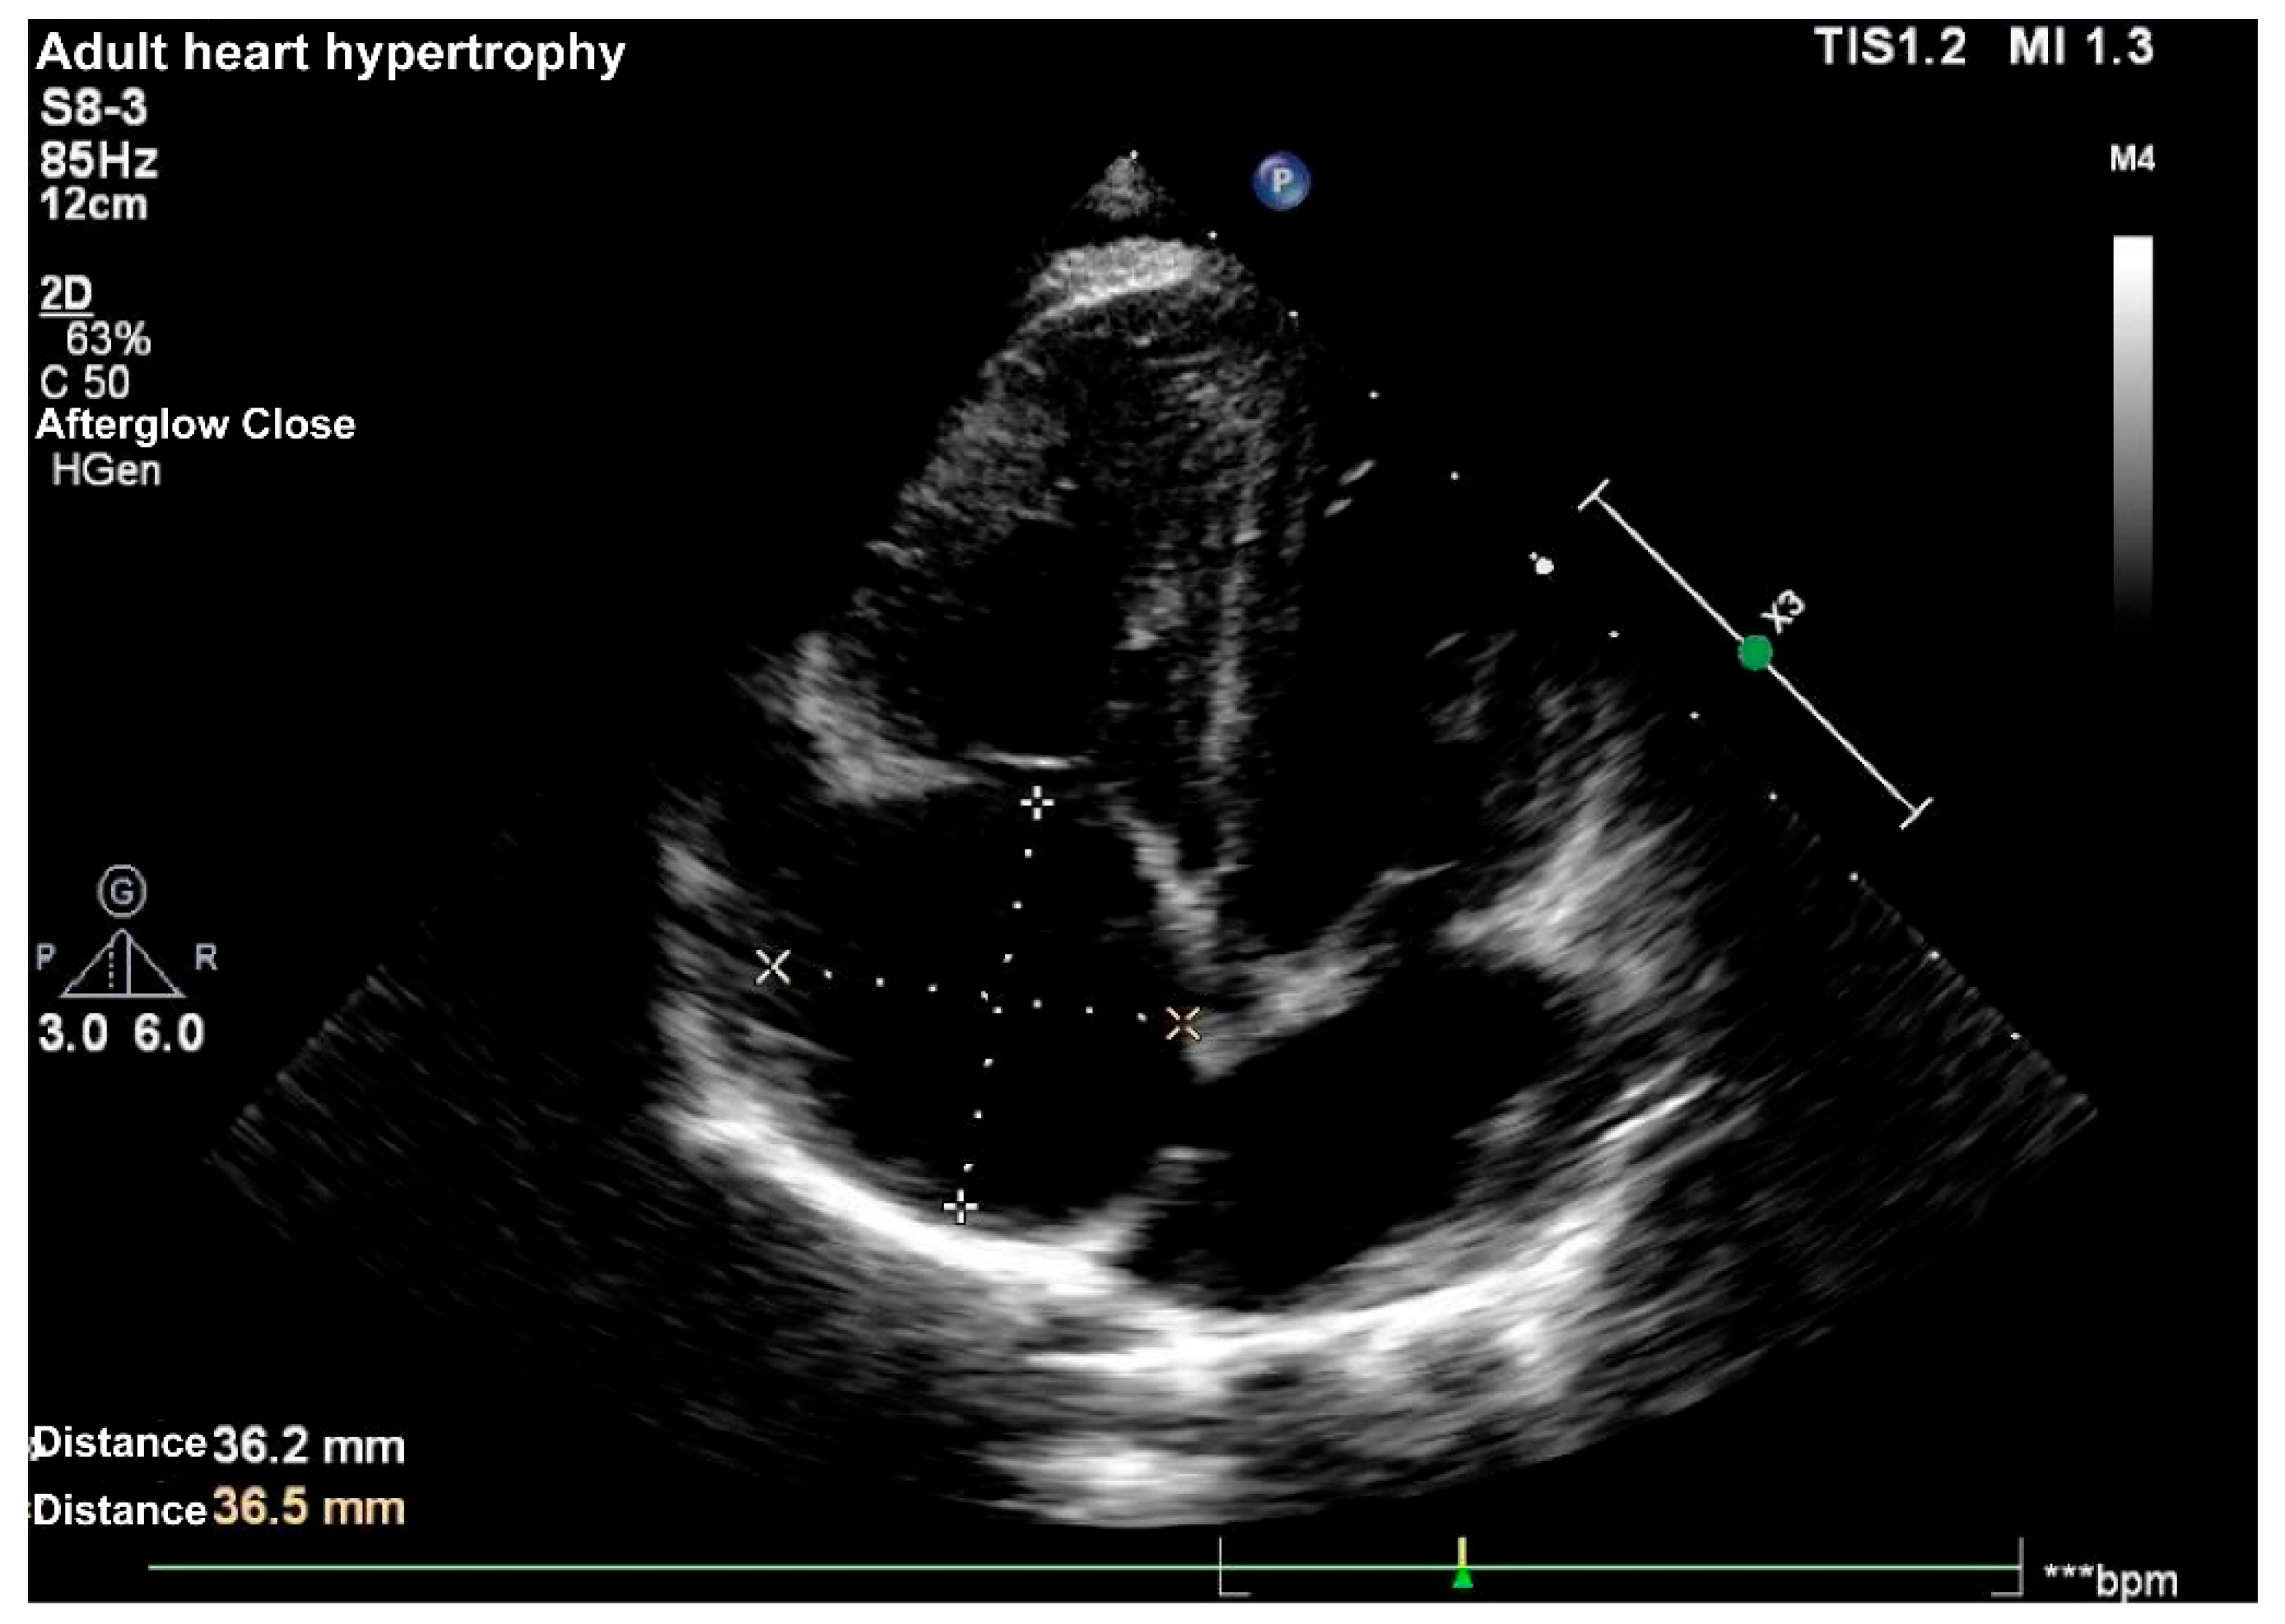

Supplementary Material FileA 7-year-old girl was taken to Women and Children’s Hospital, Qingdao University for a heart murmur. Echocardiography (Echo) showed atrial septal defect (ASD) of 13 mm (Fig. 1) with enlarged right atrium and right ventricle, slightly dilated pulmonary artery (17 mm), and left ventricular ejection fraction (LVEF) of 65%. Due to severe scoliosis, the girl underwent five spinal operations and dual growth rods at Beijing Children’s Hospital. It is indicated by our physical examination that the child had a thoracic deformity with left chest collapse.

Figure 1: Apical four-chamber view of the heart revealing dilated right atrium and right ventricle and the atrial septum deleted 13 mm.